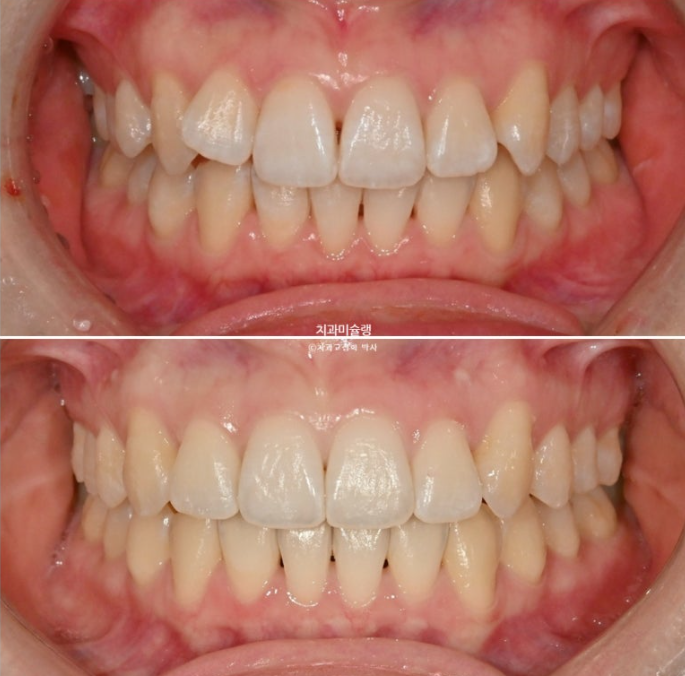

정면사진에서 블랙트라이앵글, 중심선 불일치 등이 보입니다.

덧니쪽으로 중심선은 치우치기 마련이지만 그 이외에도 양쪽 어금니 교합관계가 다르다 보니 중심선 불일치가 크게 나타납니다.

중심선 불일치가 미세하게 남았지만 만족스럽게 개선되었으며

이제 전후 비교 보겠습니다.

치료기간은 10개월 입니다.

2025.01~25.11

25.01~25.11

윗니 정중앙 블랙트라이앵글은 치간삭제를 통해 줄였으며

중심선은 처음에 비해 많이 개선되었습니다.